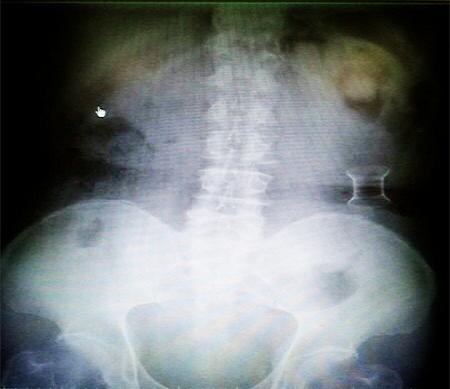

受試患者在結(jié)腸端端吻合術(shù)中,使用我司新研制產(chǎn)品達(dá)到了理想的預(yù)期效果?;颊咝g(shù)后7天、14天X光片顯影,可降解腸道支架均能按研制設(shè)計(jì)的預(yù)期時(shí)間節(jié)點(diǎn)保持應(yīng)有強(qiáng)度,術(shù)后21天X光片顯示可降解腸道支架已完全破碎,并排出體外。在整個(gè)試驗(yàn)過程中,病患無任何不良反映,耐受良好。